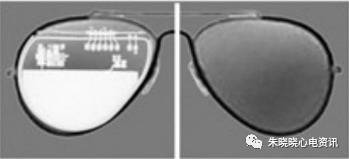

波士顿科学起搏器外形和太阳镜片类似(图4),

图4 波士顿科学起搏器

百多力起搏器怎么样通过胸片识别起搏器的简易三步法_https://www.jmylbn.com_新闻资讯_第7张